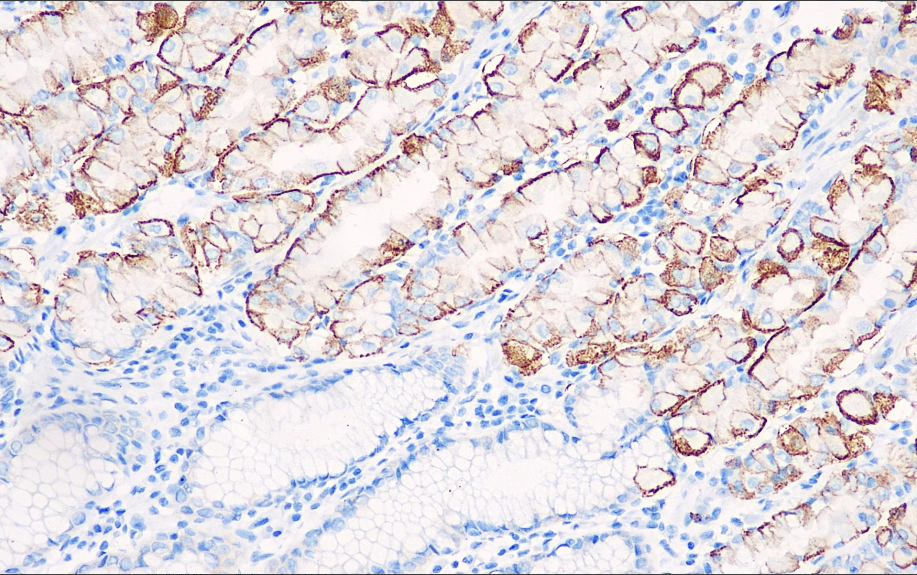

Cellular Localization: Cytoplasm/Membrane

Suitable Tissue: Paraffin/Frozen

Positive Control: Stomach

MRP is a glycoprotein with a molecular weight of 190kD and is an important reference for tumor chemotherapy resistance. Research has confirmed that MRP not only directly expels drugs, but also isolates drugs intracellularly, affecting drug redistribution and indirectly producing resistance by preventing drugs from binding to target sites. This antibody is mainly used in research on cell resistance.

MRP antibody reagents can specifically bind to MRP molecular antigens. Immunohistochemistry kits containing MRP antibody reagents are suitable for assessing multidrug resistance in tumors (such as leukemia, lung cancer, and ovarian cancer).